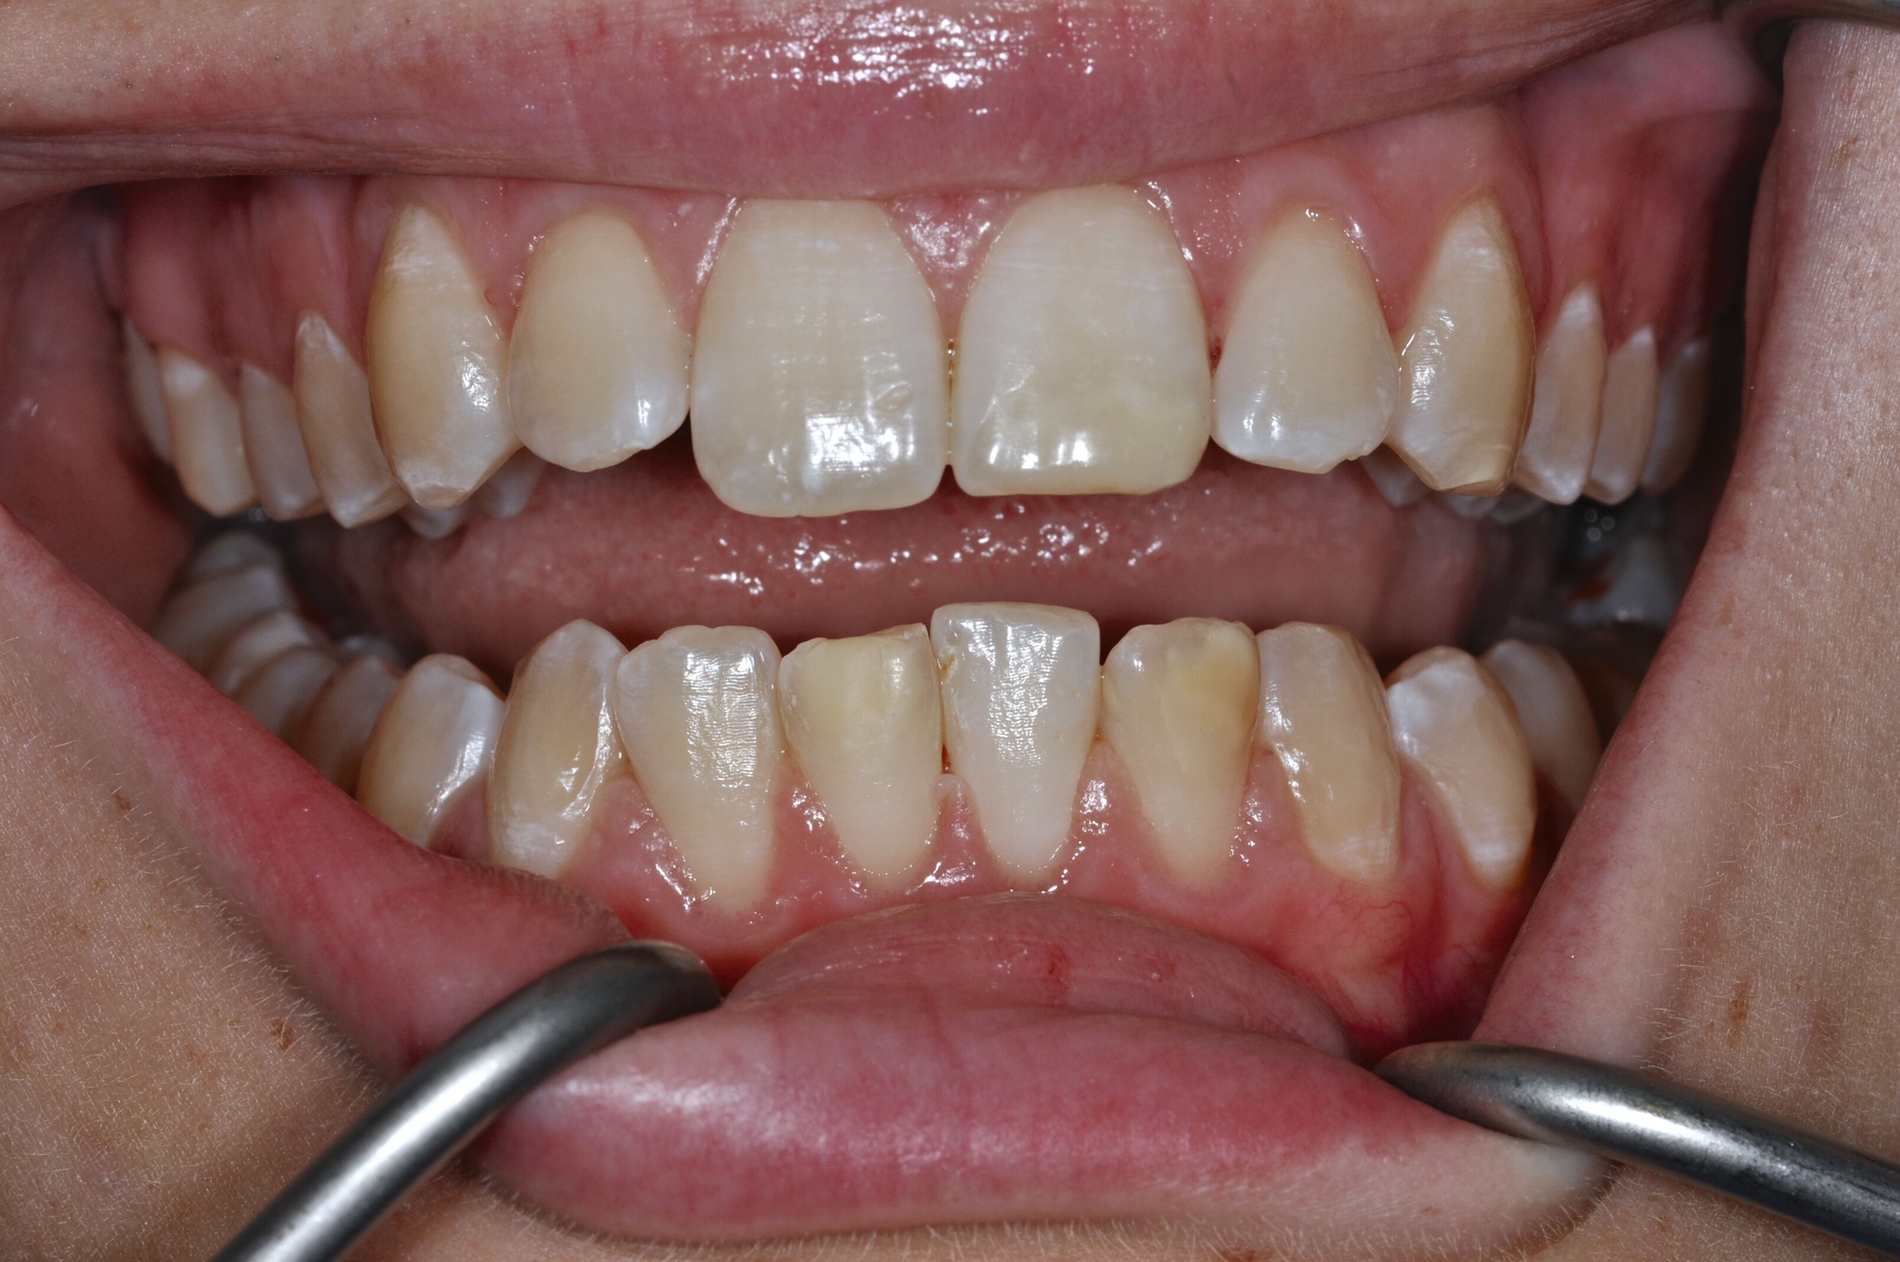

Diese Klassifikation dient als Grundlage für die Therapieempfehlungen. Deutlich wird, dass aufgrund der Symptomatik die Therapie der Zähne höchst unterschiedlich ausfällt. Dass etwa eine Opazität ohne Überempfindlichkeit (Index 1, Abbildung 1) ein anderes therapeutisches Vorgehen erfordert als ein Zahn mit nahezu komplettem Einbruch der Zahnoberfläche und mit Hypersensitivität (Index 4, Abbildung 2), ist offensichtlich.

Die temporäre Therapie C (kurzfristig)

Die Therapie C hat das Ziel, MIH-Zähne vorübergehend zu versorgen, bis der vollständige Durchbruch der Zähne eine adhäsive Restauration ermöglicht, um die hypersensiblen Zähne zu desensibilisieren oder/und die Mitarbeit für die weitere Behandlung aufzubauen. Vor dem Hintergrund des erhöhten Kariesrisikos dieser Zähne (Abbildung 2) muss durch die Maßnahmen eine Kariesprogression vermieden werden.